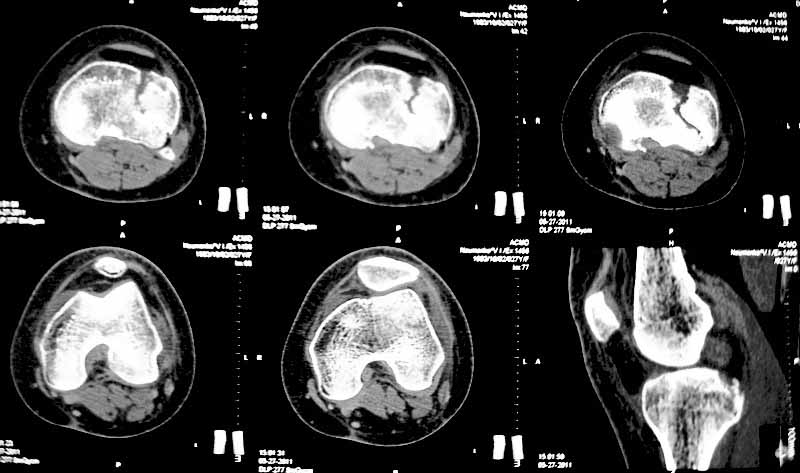

Застарелый перелом наружного мыщелка б.берцовой кости |

Уважаемые коллеги. Хочу представить вам клинический случай и получить информацию в отношении тактики лечения данной пациентки. Возраст 27 лет, парапланеристка, получила травму в Индии 28 апреля 2011г, упала с мотоцикла, получила боковой удар по левому коленному суставу. Первая помощь оказана в индийской клинике, установлен диагноз - Ссадины левого локтевого сустава, левого плеча, левой и правой стоп, повреждение связок левого коленного сустава (не указано каких). Со слов пациентки выполнены рентгеновские снимки голени (их не отдали). Наложена циркулярная рассеченная скотч-каст повязка без захвата стопы на левую ногу, рекомендовано консервативное лечение со сроком иммобилизации 6 недель. Пострадавшая оставалась в Индии и вернулась 17 мая.

26 мая обратилась ко мне за консультацией с вопросом – можно ли снять иммобилизацию немного раньше и начать ходить без костылей?. СКТ – снимки прилагаю.

-клинически – вальгизация коленного сустава, умеренная сглаженность контуров сустава, постиммобилизационная контрактура сустава, медиальной и латеральной нестабильности сустава нет.

Интересуют вопросы: -тактика лечения: -если операция, то стандартная открытая репозиция с приподнятием мениска, обзором части сустава, подъемом импактированного фрагмента, костной пластикой и фиксацией блокированной пластиной и винтами ( в больнице ЭОПа нет) или есть другие варианты? -понимаю, что операция сложна, идеала достичь будет также сложно, но возможно ли за сустав побороться именно сейчас?, а не ждать ЛФК, реабилитации, получения результатов консервативного лечения и дальнейших артроскопий, остеотомий и пр. -какие результаты лечения можно предположительно получить после выполнения операции с улучшенным, но неидеальным сопоставлением отломков и какие результаты можно ожидать от консервативной методики, будет ли лучше? -если тактика лечения консервативная, то какие ориентировочные сроки осевой нагрузки на больную ногу, сроки перехода на трость. Буду рад выслушать все предложения. Заранее благодарен. С уважением Голиков Валерий, БСМП, Киев